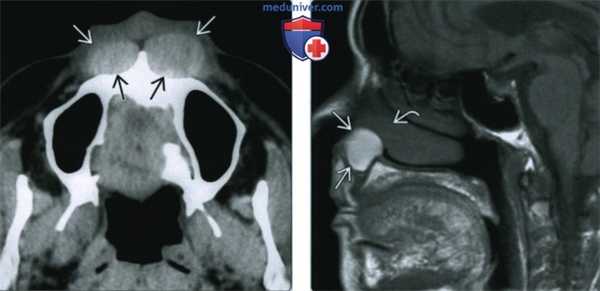

(Слева) При аксиальной КТ без контрастного усиления спереди от предчелюстной кости (с обеих сторон) визуализируются гиперденсные объемные образования округлой формы с четкими контурами. Образования вызвали выраженное ремоделирование верхней челюсти (больше слева). Носогубные кисты являются двухсторонними менее чем в 10% случаев.

(Справа) При МРТ Т1ВИ в сагиттальной проекции визуализируется носогубная киста с диффузно гиперинтенсивным сигналом, хорошо отграниченная от окружающих тканей. Обратите внимание, что верхний край кисты расположен в непосредственной близости к нижней носовой раковине и дну преддверия носа. При исследовании этих образований обнаружено, что они имеют подслизистую локализацию. (Слева) При MPT Т1 в аксиальной проекции в пределах грушевидною отверстия визуализируется хорошо отграниченное объемное образование, распространяющееся в преддверие носа. Сигнал от образования слегка интенсивнее, чем от мышц, определяются фокусы гиперинтенсивною сигнала (белковый дебрис). Обратите внимание, что объемное образование вплотную прилежит к верхней челюсти и вызывает ее умеренно выраженную эрозию по сравнению с противоположной стороной.

(Справа) При МРТ Т1ВИ в сагиттальной проекции визуализируется носогубная киста с диффузно гиперинтенсивным сигналом, хорошо отграниченная от окружающих тканей. Обратите внимание, что верхний край кисты расположен в непосредственной близости к нижней носовой раковине и дну преддверия носа. При исследовании этих образований обнаружено, что они имеют подслизистую локализацию.